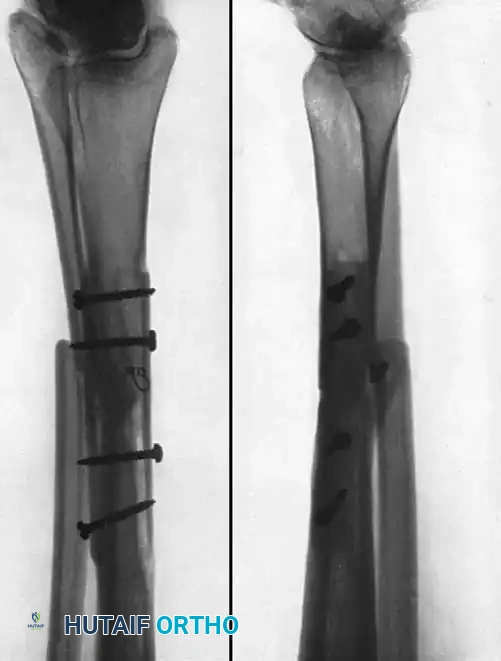

Fig. 56-20 A, Nonunion after osteotomy. Failure to produce union by sliding inlay graft; fibula is intact. B, Four years after application of dual onlay grafts and osteotomy of fibula.

Fig. 56-21 A, Oblique comminuted fracture of proximal third of tibia. B, Satisfactory restoration. C, Fracture of shaft failed to unite; treated by dual onlay graft.

In the past, most nonunions of the tibial shaft were treated with a massive cortical onlay bone graft with satisfactory results. While this method is rarely used today due to the advent of locked intramedullary nailing and locking plate technology, it remains a historically significant technique that is occasionally useful for nonunions in the extreme proximal or distal fourth of the tibia, or when dealing with severely sclerotic fragments where intramedullary instrumentation is impossible.